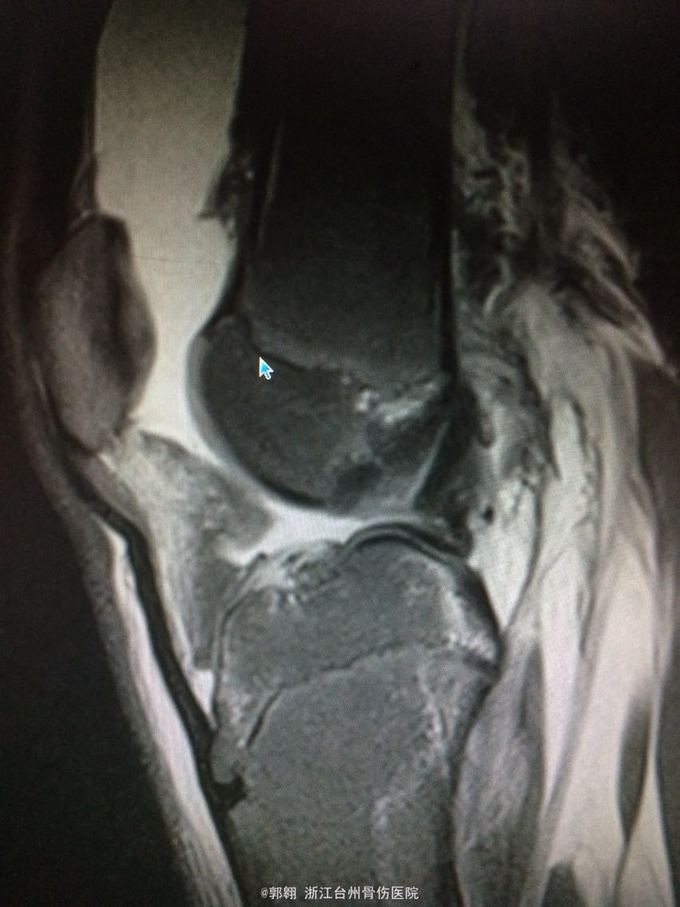

右膝关节跑步摔伤疼痛功能障碍3小时 病史:患者15岁 上体育课时跑步摔倒致右膝关节畸形疼痛 功能障碍,由老师送至医院就诊。

查体:右膝关节及小腿上段肿胀明显,张力较大,压痛位于内侧副韧带股骨处和膝关节外侧,膝关节波动感,浮髌试验阳性、扳膝试验阳性、抽屉试验阳性、Lachman阳性、膝关节屈伸活动因疼痛而障碍,足背动脉波动良好。 MRI:右膝关节股骨内髁骨折 胫骨平台外侧缘骨折

诊断:右膝关节内侧副韧带撕裂 前交叉韧带损伤 股骨内侧髁骨折胫骨平台外侧缘骨折 腓肠肌肌肉拉伤 处理:制动 支具托固定 冰敷 退肿止血药物治疗